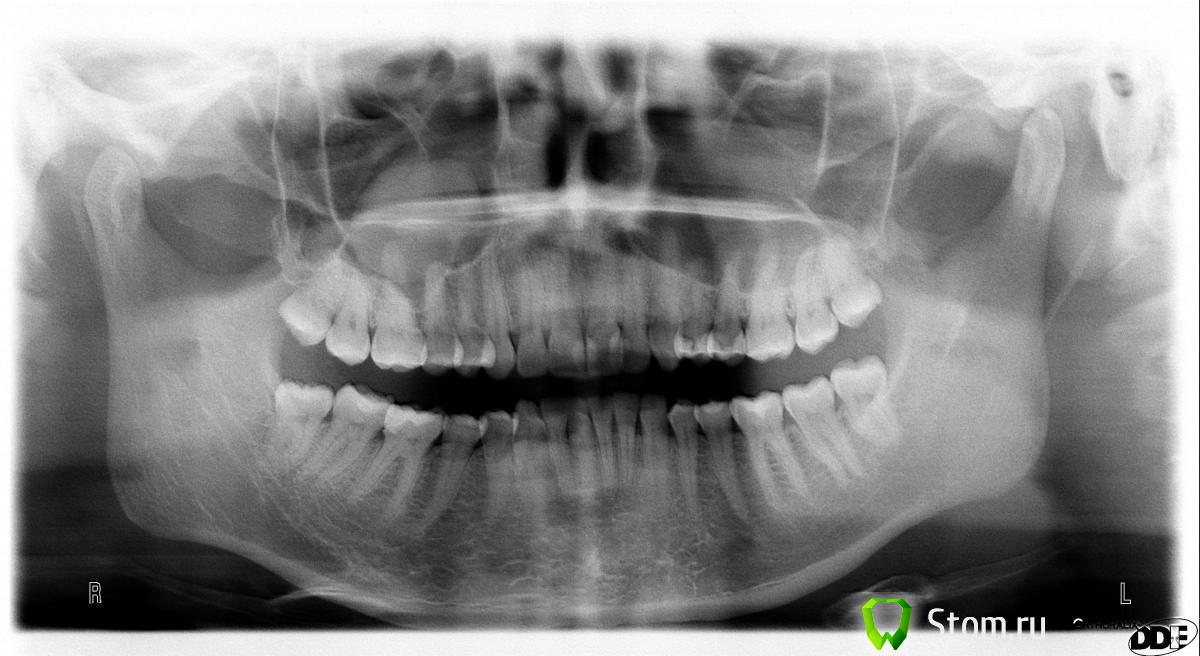

kriokov Опубликовано 6 января, 2012 Поделиться Опубликовано 6 января, 2012 -сосудосуживающие капли в левый носовой ход назначил бы, любые которые переносит, на 5-7 суток- имхо, там в правой пазухе пневматизация снижена, на мукоцеле смахивает, но оптг однозначно не скажешь, а в левой вроде спокойно. Ссылка на комментарий

ARislanV Опубликовано 14 января, 2012 Автор Поделиться Опубликовано 14 января, 2012 А правильно ли я понял по снимку, что во 2 секторе корни всех зубов в гайморовой пазухе? Ссылка на комментарий

kriokov Опубликовано 15 января, 2012 Поделиться Опубликовано 15 января, 2012 А правильно ли я понял по снимку, что во 2 секторе корни всех зубов в гайморовой пазухе?по ОПТГ не определишь что в пазухе, что нет. Видно, что пневмо тип строения пазухи. Ссылка на комментарий